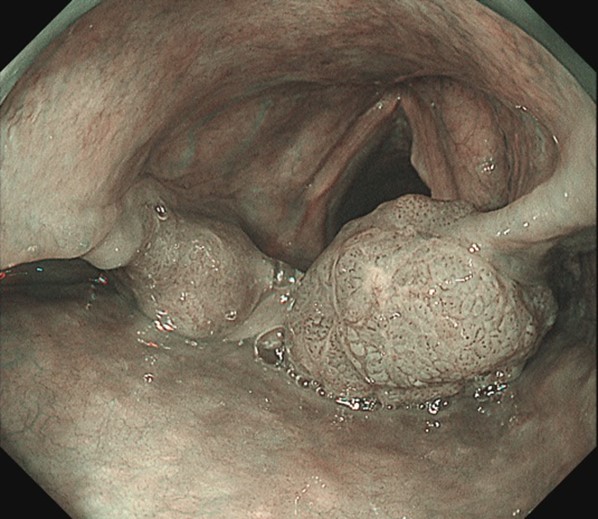

右披裂部の咽頭がん

早期十二指腸がん